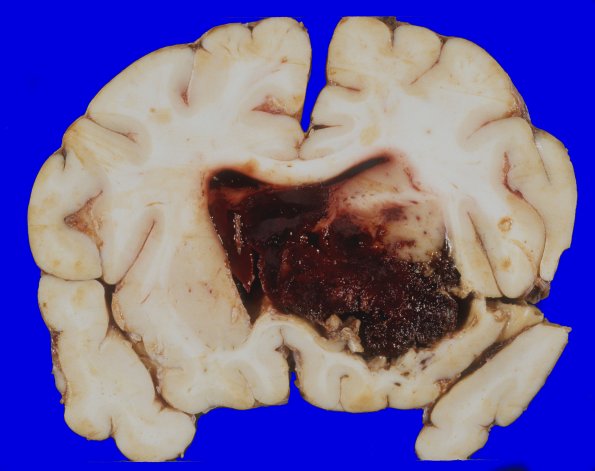

A coronal section shows an acute hemorrhage (6.5 x 6.5 x 4 cm) centered on the right basal ganglia with extension into the lateral ventricles. The hemorrhage extends from the level of anterior basal ganglia to the anterior edge of the thalamus with lateral extension into the putamen and appears to have ruptured medially into the lateral ventricles. From there, the hemorrhage has extended throughout the ventricular system, through the foramina of Magendie and Luschka and into the region of the cisterna magnum. The right cingulate shows subfalcine herniation.